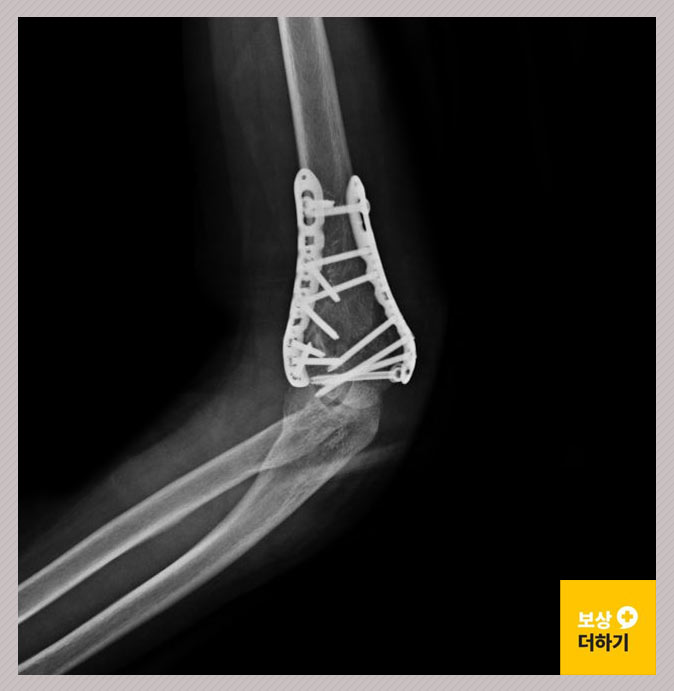

위 사고로 수술이 진행되었는데요. 금속 고정술을 받고 18일간 입원하셨습니다. 관절 부위는 외상 후 강직이 발생하기 쉽기 때문에 재활치료도 열심히 받으셨습니다.

저희는 사례자 최 00 님의 의무 기록 및 영상 CD 등을 검토하여, 장해 평가 시 누락 없이 진행될 수 있도록 필요한 준비들을 철저히 하였습니다. 이후 공신력 있는 의료기관에서 객관적인 의사의 소견을 받았고, 이러한 의학적 근거에 따라 손해사정서를 작성하여 제출할 수 있었죠. 최대한 적게 지급을 하려고 하는 보험사와의 분쟁이 있었기 때문에 여러 차례 의견이 추가적으로 오갔는데요. 이러한 쉽지 않은 과정의 결과, 후유장해 보험금 1,500만 원을 지급받을 수 있었습니다.